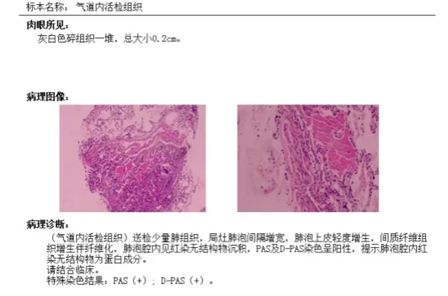

杨闪闪副主任医师为他安排了支气管镜粘膜活检,病理检查结果证实了判断:过碘酸希夫染色(PAS)阳性。最终,孟师傅被确诊为肺泡蛋白沉积症。